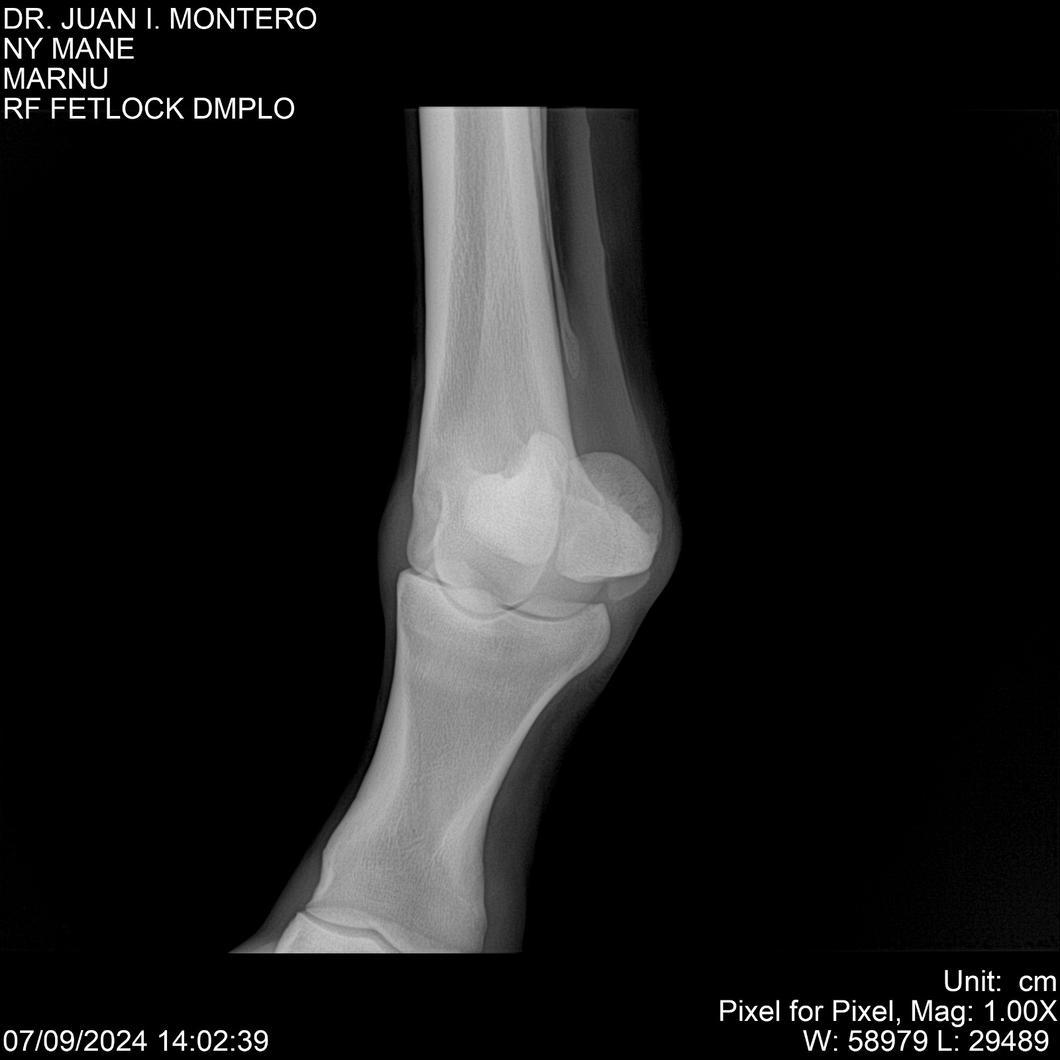

LOTE 20, NY MANE Lote Anterior Volver al remate Lote Siguiente Ficha Contacto Montevideo - Ficha del Lote Identificador: #282520 Categoría: Yeguarizos 76 Visualizaciones ClicData Contacto Empresa: Abelenda N. R., Walter Hugo Nombre*: Teléfono* : E-mail* : Mensaje Enviar Registrese gratis Este contenido Exclusivo está disponible sólo para usuarios registrados Ingresar